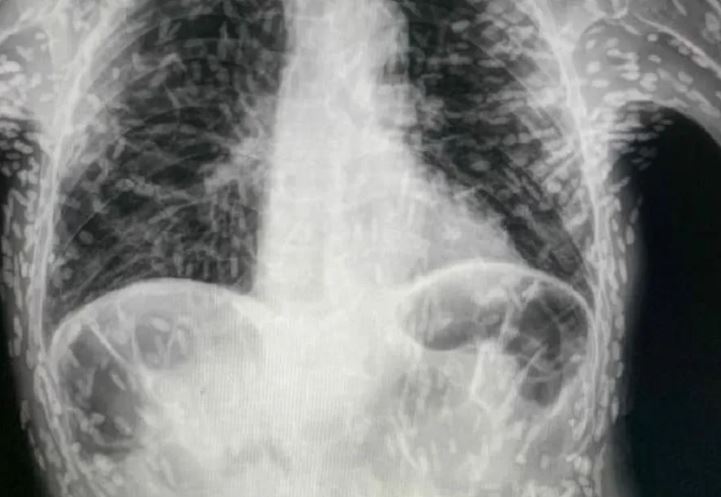

Viralizou nas redes sociais uma imagem de raio x, que mostra um paciente cheio de ovos de tênia pelo corpo, verme popularmente chamada de 'solitária'. A imagem foi publicada por um médico residente pelo Hospital das Clínicas de Botucatu, São Paulo.

A radiografia mostra um quadro de cisticercose, doença parasitária causada pela ingestão dos ovos de tênia.

O médico disse que o paciente foi procurou o hospital com quadro de tosse constante há dois meses, e através dos exames de imagem, foi constatado que os ovos já estavam mortos e calcificados.

A cisticercose é causada por cistos da larva da Taenia solium nos tecidos, e pode ser adquirida através de alimentos, água ou superfícies contaminadas com fezes.